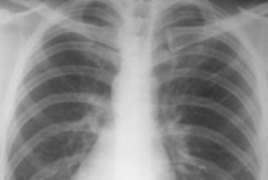

Европейские эпидемиологи выступили с предупреждением: в Британии бродит убийственный штамм пневмонии, который поражает в целом здоровых людей средних лет, заразившихся гриппом, пишет The Telegraph. Всего за один месяц врачи насчитали рекордное число заболевших.

Люди, заразившиеся штаммом, могут умереть за 3-4 часа. Поэтому наличие эффективных антибиотиков не всегда спасает. На данный момент насчитывается четверо погибших. С 6 декабря по 7 января были зафиксированы 18 случаев внебольничной пневмонии. Обычно же за весь год регистрируется 30-40 случаев. В чем причина подъема заболеваемости, специалисты сказать не могут.

Инфекцию вызывает ПВЛ-положительный стафилококк. Он отличается повышенной агрессивностью. Его переносят на коже примерно 3% населения. Обычно он провоцирует болезни кожи и фурункулы. Однако патоген способен проникать в кровоток, добираясь до легких. Развитие инфекции протекает бурно (возможен кашель с кровью, затрудненное дыхание).

Известно, что всем 18 заразившимся британцам (возраст от 4 до 63 лет; пятеро подхватили инфекцию от родных) требовалась интенсивная терапия. А некоторых даже пришлось подключить к системе ЭМО (экстракорпоральная мембранная оксигенация, предполагающая насыщение крови кислородом вне тела и ее обратное введение).